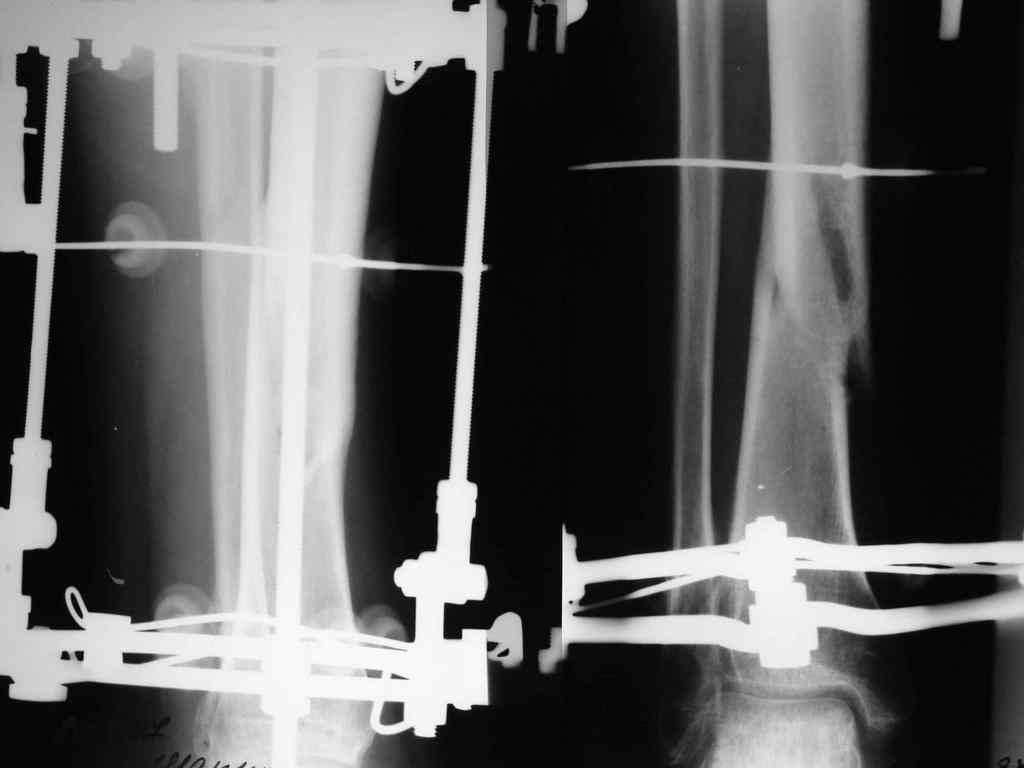

И ещё: Имеется у нас пациент с переломом обеих костей левой голени. Перелому 13 месяцев. После 6-ти месяцев фиксации в гипсе был наложен аппарат Илизарова.

После коррекции длинны и оси конечности аппарат стабилизирован. В аппарате 7 месяцев. Последние снимки прилагаются. Консультирован на консультативном приёме в УНИИТО. Рекомендовано ослабить аппарат на 20 мм.(!) и ходить с полной нагрузкой на конечность. Убедительная просьба рассмотреть вариант лечения данного пациента в условиях УНИИТО (МОС блокируемым стержнем), т.к. пока не располагаем набором развёрток.

Если судить по рентгенограммам, то перелом сроссЯ, причем месяца два назад. Проведите клиническую пробу, и не надо ничего усложнять.

Согласен с оценкой Александра Артемьева. Не могли бы Вы пояснить, какие соображения при таких рентгенограммах мотивируют к реостеосинтезу?

Перелом сросся.

Снимайте аппарат.

Ходьба с постепеннымвозрастоанием нагрузки на поврежденную конечность.